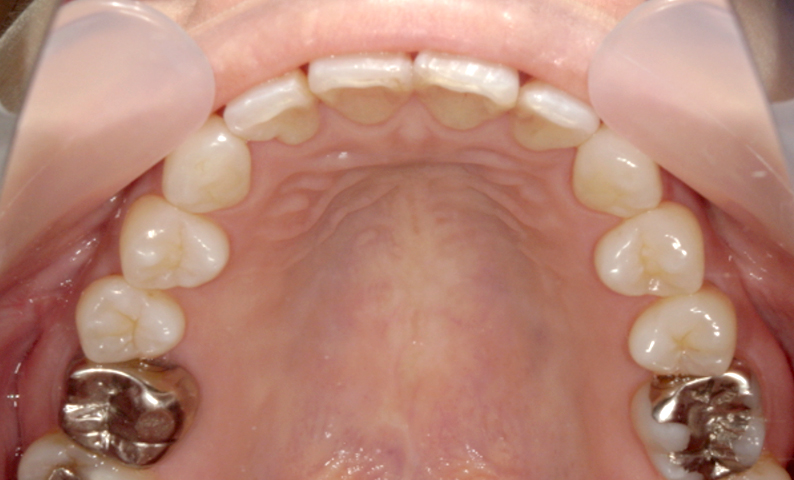

症例_001 前歯「捻転歯」症例

治療期間:6ヶ月金額:48万円+税20代女性少しのねじれ捻転歯下の八重歯

| Before | After |